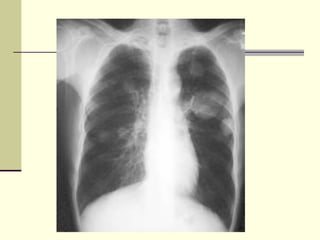

PLEURAL EFFUSION Fluid accumulates in the pleural space. Radiological criteria  are:  Increased Density  In dependent portion Costophrenic angle in PA view  Along sides in lateral decubitus position  Along posteriorly in supine position, giving diffuse haziness on the side of effusion  Blunting of costophrenic angle   Lack of identifiable diaphragm  (silhouette sign principle).

PLEURAL EFFUSION Fluidaccumulates in the pleural space. Radiological criteria are: Increased Density In dependent portion Costophrenic angle in PA view Along sides in lateral decubitus position Along posteriorly in supine position, giving diffuse haziness on the side of effusion Blunting of costophrenic angle  Lack of identifiable diaphragm  (silhouette sign principle).